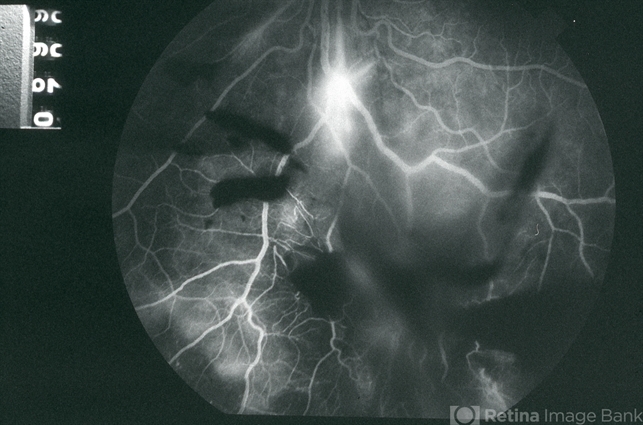

- EALES DISEASE

- Eales disease, neovascularization elsewhere (NVE), vitreous hemorrhage, fluorescein angiogram (FA), FA late phase, FA late phase leakage

- Mid-phase (70 seconds) fluorescein angiogram image of the inferior periphery OS of a 20-year-old Vietnamese male with Eales Disease; there is bright hyperfluorescence from a focus of NVE below the optic disc and blocked fluorescence from vitreous hemorrhage in the eye.